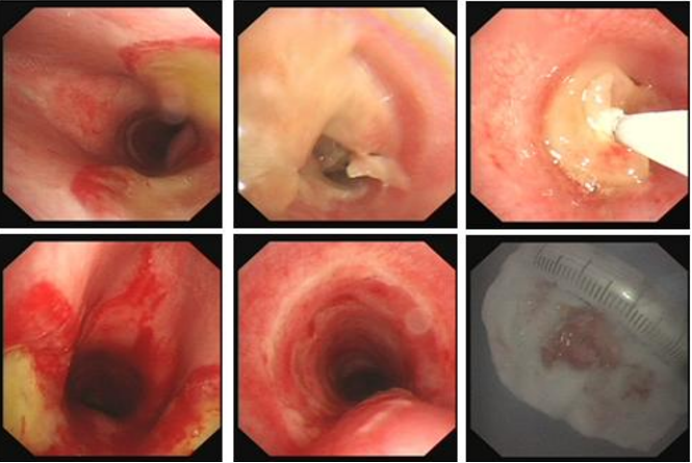

病例4

16岁男性患者, 突发意识障碍2个月入院, 有两次气管插管史及51天气管切开史, 金属套管堵管失败, 气管镜示声门下气管上段狭窄。我院复查气管镜显示气管上段瘢痕形成完全堵塞气道, 活检钳及生理盐水加压注射均无法通过。全院大会诊后, 家属拒绝外科手术, 选择内镜介入治疗。静脉麻醉下拔除金属导管, 尝试穿刺置导丝失败后, 采用针形电刀切开瘢痕(图5),逐步扩张狭窄段(最终14 mm无法通过),夹除坏死物后成功置入T管,术后患者病情稳定。

图片

5  针形电刀环切并置入T管